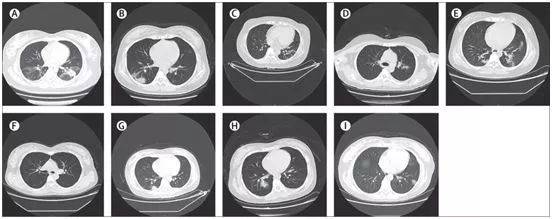

9名感染COVID-19的孕妇的胸部CT扫描图(横断面),图片来自The Lancet, 2020, doi:10.1016/S0140-6736(20)30360-3。